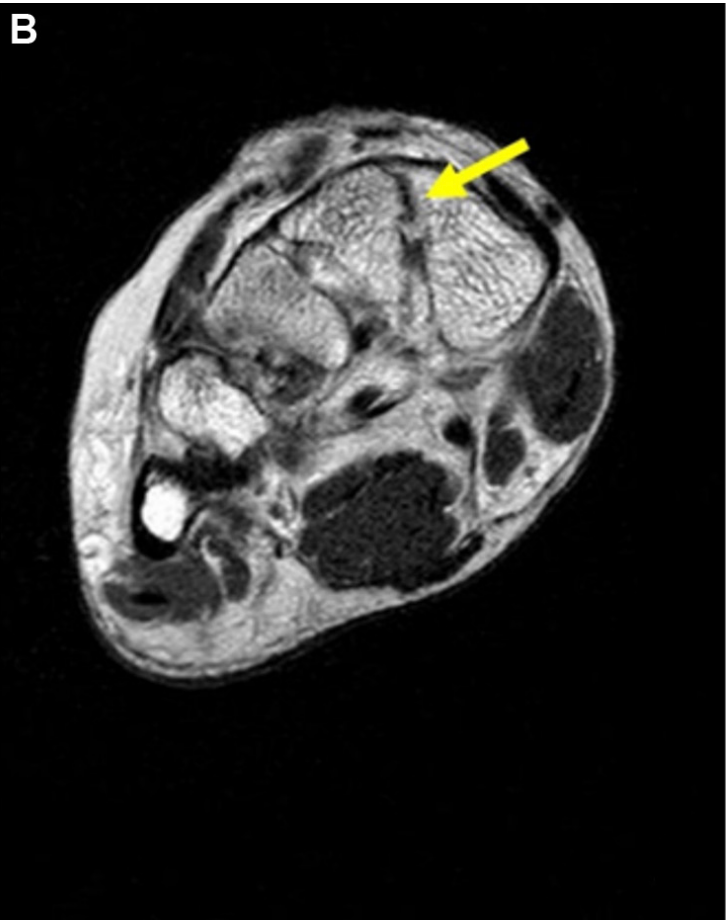

▲图示术前Lisfranc韧带的磁共振成像(MRI)评估:可见Lisfranc韧带断裂(黄色箭头标记)。